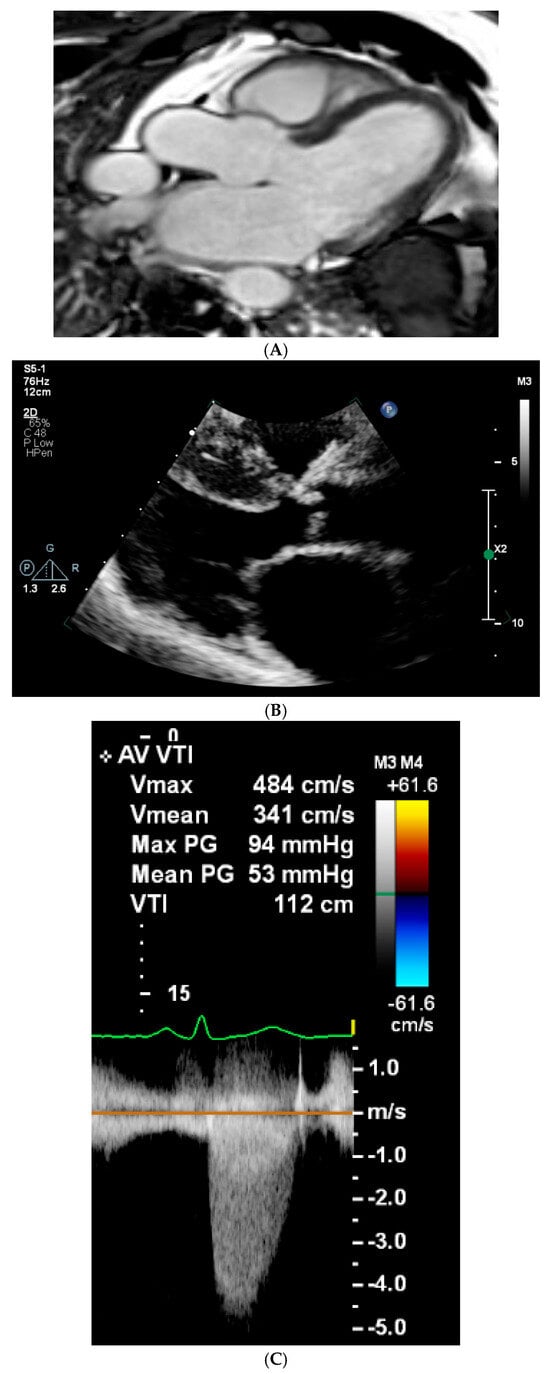

| MPS VI (Case 6) | Childhood—hip replacement and hearing impairment | 46/F | 147 | 54 | 25.2 | Arylsulfatase B 0.6 nmol/mg/h (7–108) | ECG: N ECHO: Severe AS, mitral thickening, mild mitral regurgitation | ENT: Adenoidectomy at 29 yr Crowded oropharynx, high anterior larynx, bulky epiglottis Short cervical spine, restricted neck extension Sensorineural hearing | None | Right hip replacement Maxillary slightly hypoplastic | Poor memory, no other cognitive impairment; mild syrinx at C7 no gross cord signal abnormalities; possible Chiari I malformation. | None |